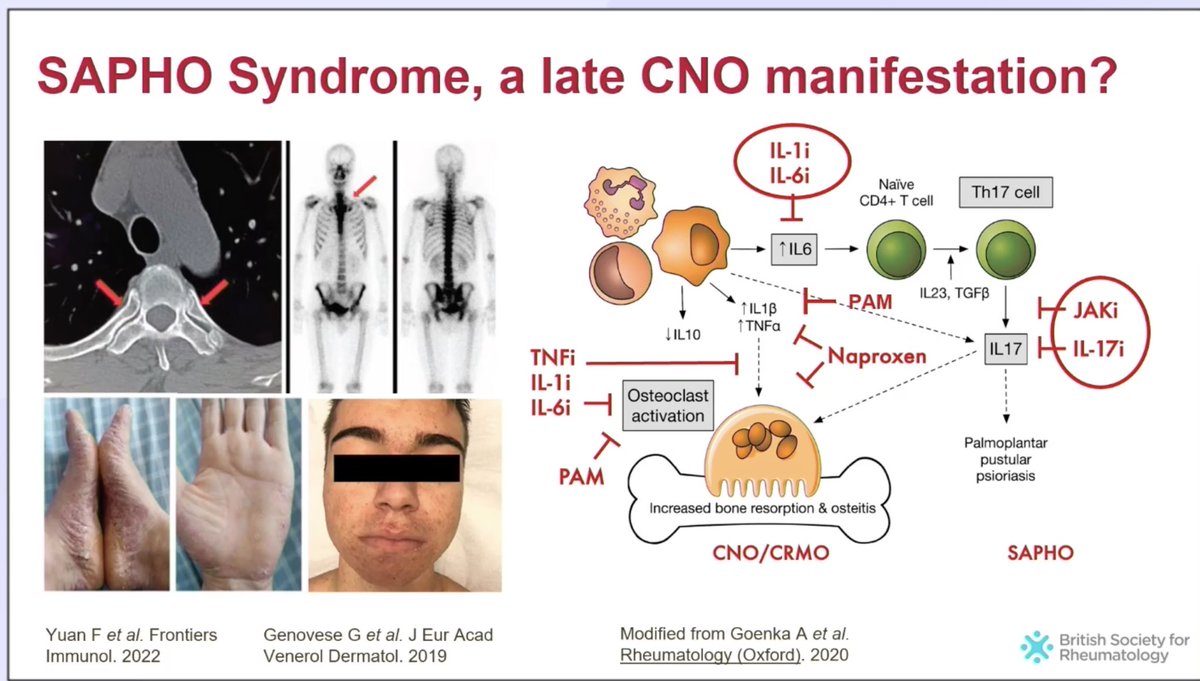

Encantado de participar con los Dres Benavent (H Bellvitge) y Corominas (H SPau) en la Mesa de Imagen del #SimposioAR24 Soc.Esp.Reumatología